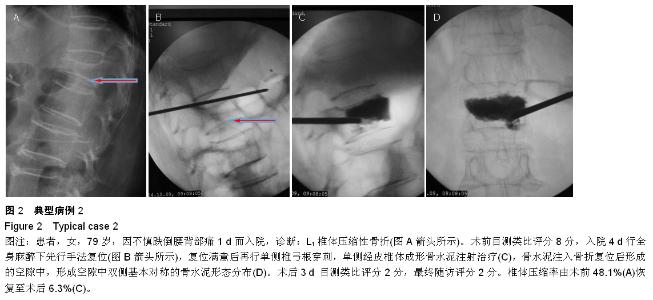

METHODS: A total of 53 patients with single vertebral osteoporotic vertebral compression fractures, who were treated with percutaneous vertebroplasty, were retrospectively analyzed from July 2012 to December 2014. The new method group (32 cases) received manual reduction, underwent unilateral pedicle puncture and bone

cement injection during unilateral percutaneous vertebroplasty under general anesthesia. The conventional method group (21 cases) received conventional percutaneous vertebroplasty.

RESULTS AND CONCLUSION: There was an average of 6-month follow-up (3-14 months). Significant differences in visual analogue scale scores, vertebral compression ratio and kyphosis Cobb’s angle were detected in the new method and the conventional method groups at 3 days post surgery and during final follow-up compared with before surgery (P < 0.01). No significant difference in visual analogue scale scores was found between the two groups (P > 0.05). Compared with the conventional method group, postoperative vertebral compression ratio, kyphosis Cobb’s angle and bone cement leakage rate were significantly lower in the new method group (P < 0.01). Results verified that the new method combined with the advantages of percutaneous vertebroplasty and percutaneous kyphoplasty, the advantages of unilateral and bilateral puncture approach. The new method can correct kyphosis deformity, effectively recover the vertebral height and physiological curvature and the puncture is safe. Simultaneously, the leakage rate of bone cement is reduced, and the distribution of bone cement is ideal.